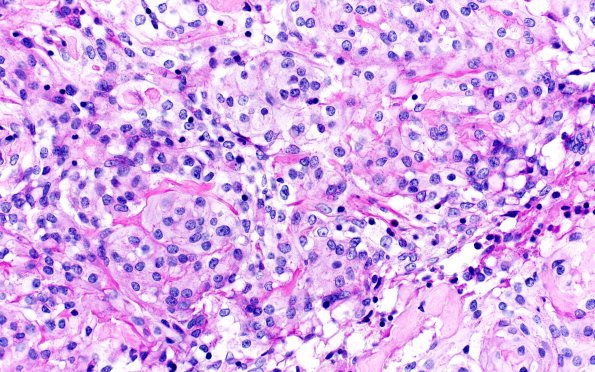

Washington University Experience | NEOPLASMS (MENINGIOMA) | Meningioma - Clear cell | 20C3 Clear cell meningioma (Case 20) PAS 40X 2

PAS staining in clear cell meningioma may be subtle, as in this case, but comparison demonstrates a diastase effect.